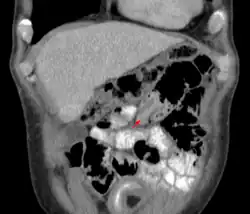

Pequena invaginação intestinal em tomografia computadorizada

Um raio-x de abdômen pode ser indicado para verificar obstrução intestinal ou gás intraperitoneal livre. A última constatação implica que a perfuração intestinal já ocorreu. Algumas instituições utilizam enema de ar para o diagnóstico, e o mesmo procedimento pode ser utilizado para tratamento.[5]